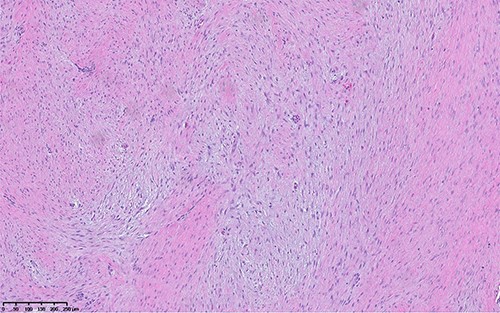

Immunohistochemistry performed for B-catenin shows strong nuclear staining, indicating molecular alteration in CTNNB1 gene. Without the mutation, we see cytoplasmic staining.

The histologic examination of the resected specimen revealed benign fibroblastic spindle cell tumors focally infiltrating into muscular tissue (Fig. 5). Immunohistochemistry revealed positivity for B-catenin and focal positivity for smooth muscle actin (Fig. 6). Ki-67 proliferation index was low (2%). The spindle cells were negative for desmin, CD34 and keratin. This was consistent with desmoid fibromatosis. The pathological assessment was critical in obtaining a definitive diagnosis.